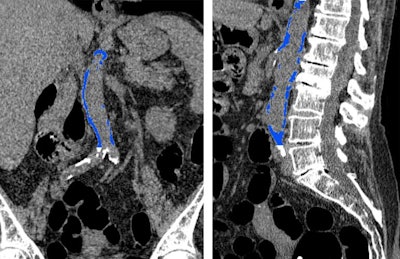

The researchers used a semiautomated CT software tool (V3D-Calcium Scoring, Viatronix) to segment and quantify abdominal aortic calcification on the CT colonography scans.

On average, they discovered that calcification in the abdominal aorta was more than five times higher for individuals who had a cardiovascular event than for those who did not experience an event (calcium score of 3,478 versus 664, p < 0.001). Thus, abdominal aortic calcification on CT was a statistically significant predictor of cardiovascular events -- better even than the Framingham risk score.